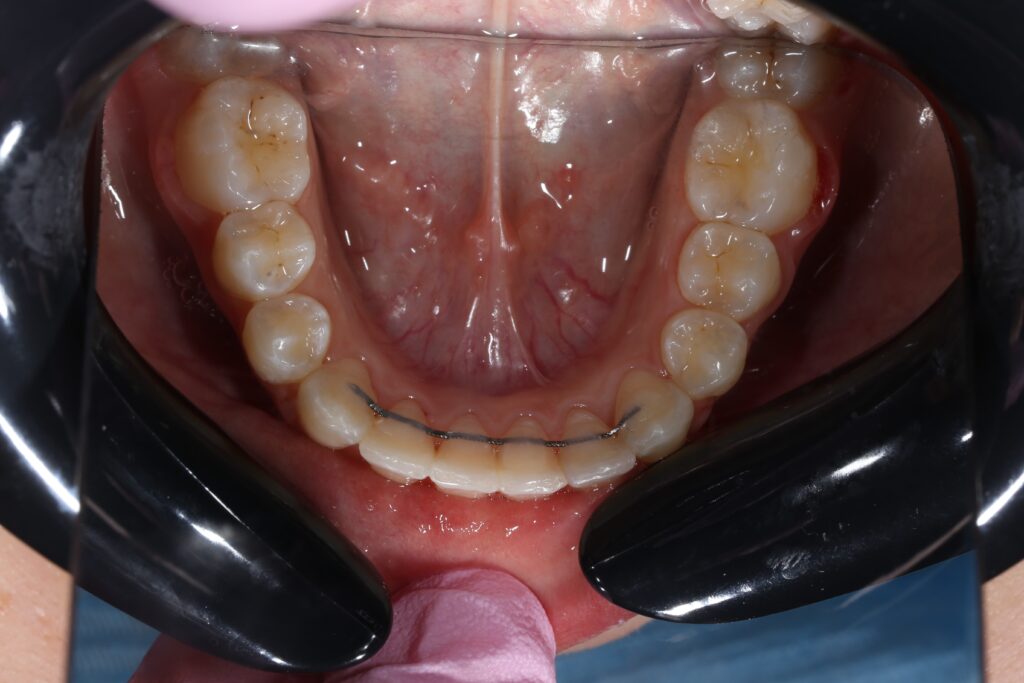

пациент после ортодонтического лечения